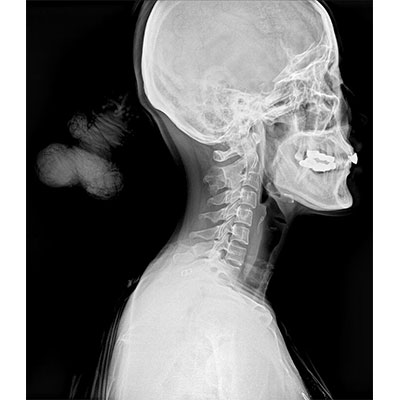

● 采用自主研發(fā)的技術(shù),在保證優(yōu)質(zhì)圖像的前提下,大大降低X射線(xiàn)劑量,用心呵護醫護工作者及患者的健康。

● 短曝光時(shí)間,便于老年人、兒童、殘疾人進(jìn)行臨床拍攝。避免這類(lèi)群體因不能有效控制身體運動(dòng)等因素造成的運動(dòng)偽影,提高攝片質(zhì)量及效率。